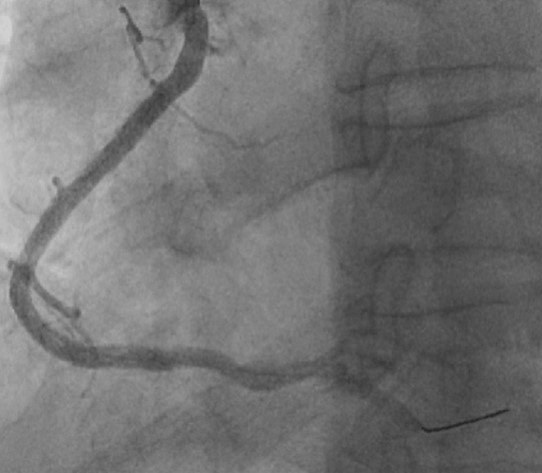

Contralateral injection approach PCI. Difficulty in wiring occluded LAD segment with Fielder XT-A and Gaia Next 2nd despite with Corsair Pro XS support. Wiring of LAD was successful after escalation to Gaia Next 3rd. After failed attempts to deliver microcatheter, 0.9mm excimer coronary laser atherectomy (ELCA) was performed for 12 cycles (60/80, blood medium) followed by predilatation with Sapphire 3 0.85/10 and Sapphire 1.5/10. Delivery of the microcatheter over the lesion was then successful. Gaia Next 3rd wire then exchanged to NS Runthrough. Predilatation of the lesion with NC Sapphire 2.0/15 and NC Trek 2.5/15, however noted balloon severe underexpansion. Optical Coherent Tomography (OCT) performed with Dragonfly Opstar showed severely calcified neoatherosclerosis. Four runs of 1.5mm burr rotational atherectomy was then performed at 180,000rpm, followed by another three runs of 1.75mm burr rotablation at 180,000rpm. We then deployed DES Xcience Skypoint 2.5/38 to m-dLAD and another DES 3.5/28 Xcience Skypoint to the LM-pLAD region due to dissection flap evident in OCT. Lesion segment between DES was subsequently prepared with intravascular lithotripsy (IVL) 3.0/12 for 80 shocks and NC Pantera Leo 3.0/15 before deploying Xcience Skypoint 3.0/15. DES optimization was then performed under OCT guidance. Finally, DCB 3.0/20 Sequent Please Neo DCB was deployed to mLAD ISR for 60 seconds. Staged PCI to RCA was performed with IVL followed by DES deployment under imaging guidance.

Case Summary